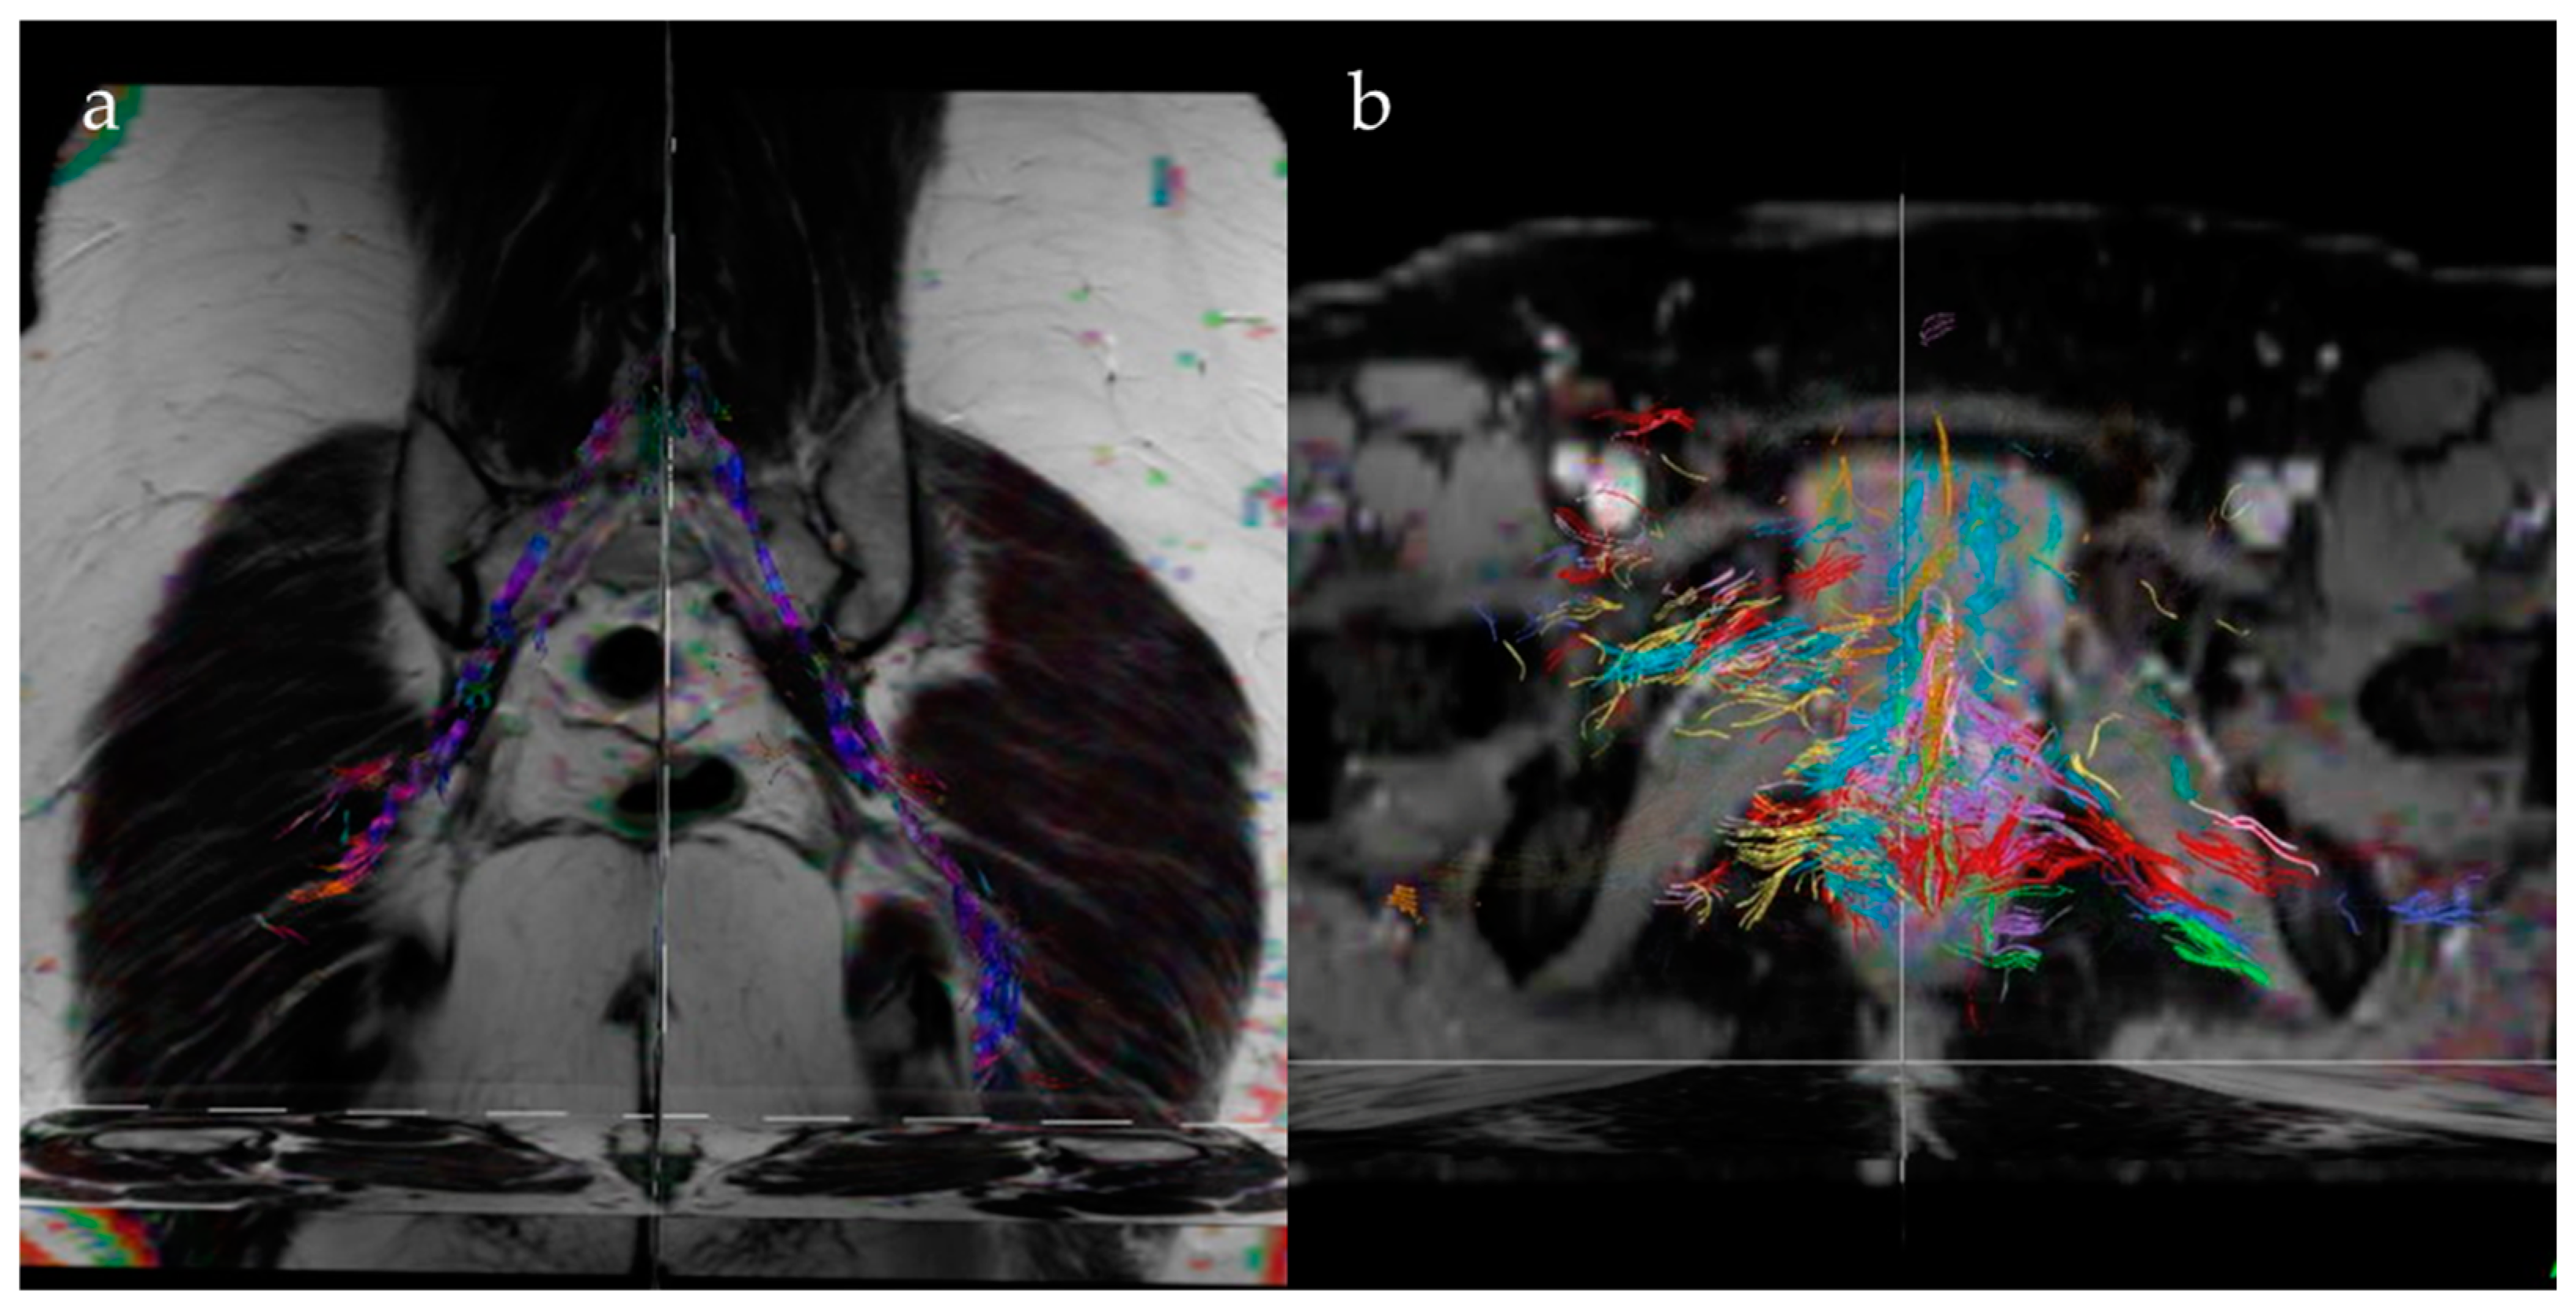

- Manganaro, L.; Porpora, M.G.; Vinci, V.; Bernardo, S.; Lodise, P.; Sollazzo, P.; Sergi, M.E.; Saldari, M.; Pace, G.; Vittori, G.; et al. Diffusion tensor imaging and tractography to evaluate sacral nerve root abnormalities in endometriosis-related pain: A pilot study. Eur. Radiol. 2014, 24, 95–101. [Google Scholar] [CrossRef]

- Porpora, M.G.; Vinci, V.; De Vito, C.; Migliara, G.; Anastasi, E.; Ticino, A.; Resta, S.; Catalano, C.; Panici, P.B.; Manganaro, L. The Role of Magnetic Resonance Imaging-Diffusion Tensor Imaging in Predicting Pain Related to Endometriosis: A Preliminary Study. J. Minim. Invasive Gynecol. 2018, 25, 661–669. [Google Scholar] [CrossRef]